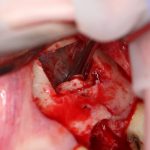

Для получения костного блока, мы открываем донорскую зону, наружную косую линию нижней челюсти.

Получение костного аутотрансплантата.

Здесь потребуется пародонтологический зонд с миллиметровой разметкой или какой-то другой измерительный прибор (операционная линейка). Ранее по КЛКТ я измерил костный дефект, теперь нужно нанести границы будущего костного блока на донорскую зону.

Ремарка: некоторые доктора предлагают делать хирургические шаблоны или выкройки специально для точного забора костного блока. На мой взгляд, это чрезмерное усложнение - во-первых, использование подобных шаблонов или выкроек требует увеличения площади раны, во-вторых, это увеличивает время и стоимость лечения, в-третьих, на этом этапе не требуется высокая точность, поскольку блок всё равно потребует адаптации.

Иными словами, важна не точность, а быстрый, аккуратный и, что главное, малотравматичный забор аутотрансплантата.

Для получения костного блока мы использовали ультразвуковую пьезохирургическую систему. Это самый удобный и безопасный инструмент для проведения подобных манипуляций. С помощью него мы сформировали и выделили костный блок. Он должен отделяться легким движением остеотома или элеватора. Как это сделать правильно — читай здесь>>

Кстати, если костный блок не отделяется от костного ложа легким движением элеватора, значит он неправильно сформирован или не до конца выделен. Вообще, любое чрезмерное усилие в хирургии — это всегда следствие рукожопия. Если тебе что-то приходится делать с усилием (установка имплантата, удаление зуба и т. д.) — значит ты делаешь это неправильно. Остановись и подумай, что именно.